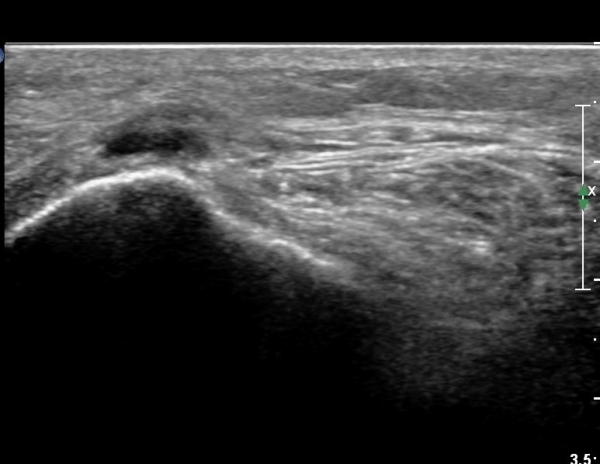

¹«¸­ ¿À±Ý ºÎÀ§ Ⱦ´Ü¸é°Ë»ç¿¡¼­ °æ°ñµ¿¸Æ Ç¥Ãþ¿¡ ºñ°ñ½Å°æ°ú °æ°ñ½Å°æÀÌ ºÐ¸®µÇ¾î °üÂûµÈ´Ù(»çÁø 1).

ŽÃËÀÚ¸¦ ¸»´ÜÀ¸·Î À̵¿ÇÏ´Ï À̵ιڱ٠³»Ãø¿¡¼­ ºñ°ñ½Å°æ¿Í °üÂûµÈ´Ù(»çÁø 2).

ŽÃËÀÚ¸¦ Á» ´õ ¸»´Ü, ¿ÜÃøÀ¸·Î À̵¿ÇÏ´Ï ºñ°ñµÎ Ç¥Ãþ¿¡¼­ ºñ°ñ½Å°æÀÌ Àú¿¡ÄÚ·Î °üÂûµÈ´Ù(»çÁø 3, 4, 5).

ŽÃËÀÚ¸¦ Á» ´õ ¸»´ÜÀ¸·Î À̵¿ÇÏ´Ï ºñ°ñ °æºÎ Ç¥Ãþ¿¡¼­ ºñ°ñ½Å°æÀÌ °üÂûµÇ°í(»çÁø 6, 7),

ºñ°ñ±Ù ½ÉºÎÀÇ ºñ°ñ °æºÎ¿¡¼­ °üÂûµÈ´Ù(»çÁø 8).

ºñ°ñ½Å°æ Á¾´Ü¸é°Ë»ç¿¡¼­ Àü¹ÝÀûÀ¸·Î ºñ°ñ½Å°æÀÇ Àú¿¡ÄÚºÎÁ¾ÀÌ °üÂûµÈ´Ù(»çÁø 9).

ºñ°ñ °æºÎ ºÎÀ§¿¡¼­ ºñ°ñ½Å°æ ¼ö¾× ¹Ú¸®¼ú ½Ã ÁÖ»ç¹Ù´ÃÀÌ ºñ°ñ½Å°æ Ç¥Ãþ¿¡ À§Ä¡ÇÏ°í ¼ö¾×ÀÌ

Á¶±Ý ÁÖ»çµÈ ¸ð½ÀÀÌ´Ù(»çÁø 10).